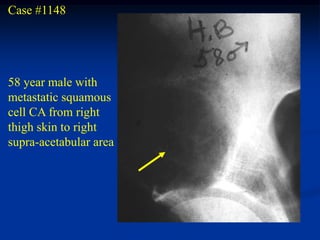

Case #1148

58 year male with

metastatic squamous

cell CA from right

thigh skin to right

supra-acetabular area

Post op appearance following an internal hemipelvectomy